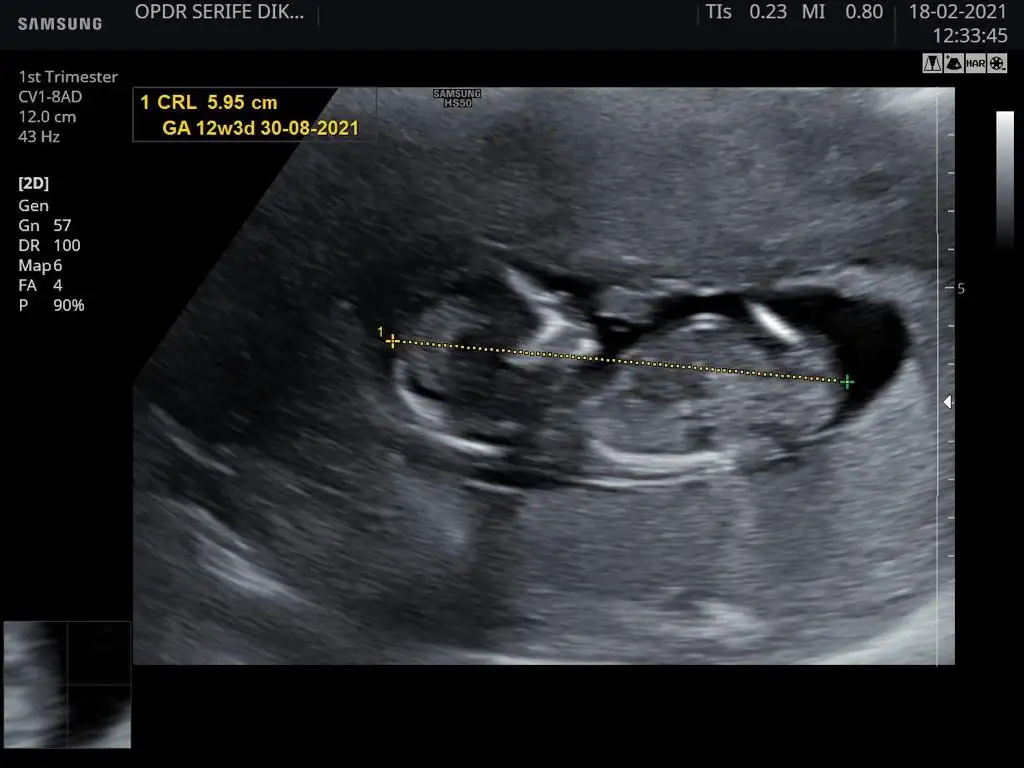

Bana da bakarmısınız karından 12 +2 günlük ultrason

22 KB · Görüntüleme: 133